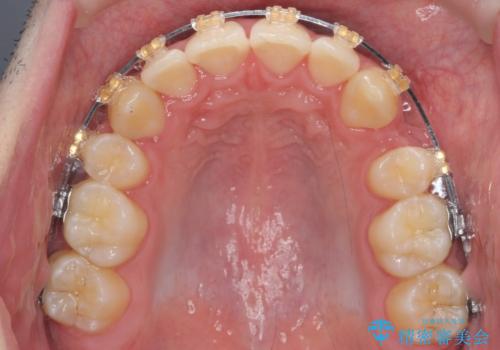

- ワイヤー矯正

- 3年3ヶ月

上下左右の小臼歯を抜歯しています。

下のがたつきが大きいため、抜いたスペースをしっかり利用して並べるため矯正用インプラントを使用しています。